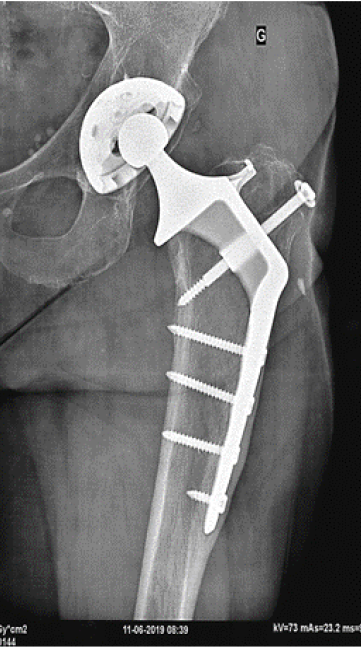

Eccentricity of the right metallic femoral head 0.7 cm loosening of polyethylene in 30 Years No calcar resorption, no screws fracture, periosteum inamovible apposition. Harris score: 100 (Figures 2-14).

Figure 11. Thirty years after surgery

Figure 12. Twenty-six years after surgery

Figure 14. Polyethylene loosening 26 Years follow-up and ≠0.015 mms per year (0.015 x 26 = 0.39)